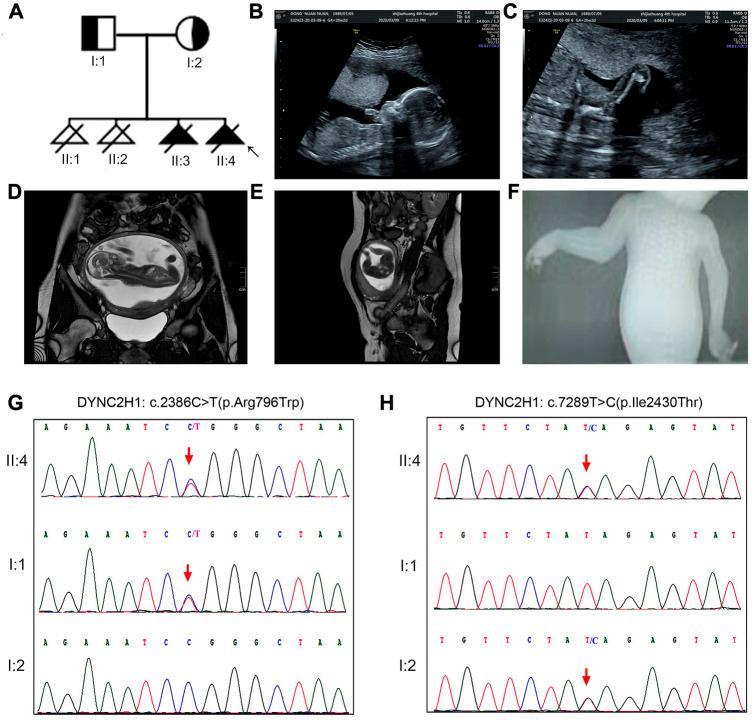

Short-rib thoracic dysplasia 3 with or without polydactyly (SRTD3) represents a type of severe fetal skeletal dysplasia (SD) characterized by shortened limbs, narrow thorax with or without polydactyly, which is caused by the homozygous or compound heterozygous mutations in the gene. SRTD3 is a recessive disorder, identification of the responsible genetic variation would be beneficial to an accurate prenatal diagnosis and well-grounded counseling for the affected families. Two families having experienced recurrent fetal SDs were recruited and submitted to a multiplatform genetic investigation. Whole-exome sequencing (WES) was performed with samples collected from the probands. Sanger sequencing and fluorescent quantitative PCR (qPCR) were conducted as validation assays for suspected variations. WES identified two compound heterozygous variations in the 2H1(NM_001080463.2) gene, namely c.2386C>T (p.Arg796Trp) and c.7289T>C (p.Ile2430Thr) for one; and exon (64-83)del and c.8190G>T (p.Leu2730Phe) for the other, respectively. One variant in them, exon (64-83)del, was novelly identified. The study detected two compound heterozygous variation in including one novel deletion: exon (64-83) del. Our findings clarified the cause of fetal skeletal dysplasia in the subject families, provided guidance for their future pregnancies, and highlighted the value of WES in diagnosis of skeletal dysplasia with unclear prenatal indications.

伴有或不伴有多指畸形的短肋胸廓发育不良3型(SRTD3)是一种严重的胎儿骨骼发育不良(SD),其特征为四肢短小、胸廓狭窄,伴有或不伴有多指畸形,由该基因的纯合或复合杂合突变引起。SRTD3是一种隐性疾病,确定相关的基因变异将有助于进行准确的产前诊断,并为受影响的家庭提供有充分依据的咨询。招募了两个经历过反复胎儿SD的家庭,并对其进行了多平台基因研究。对先证者采集的样本进行全外显子组测序(WES)。进行Sanger测序和荧光定量PCR(qPCR)作为对疑似变异的验证检测。WES在2H1(NM_001080463.2)基因中鉴定出两个复合杂合变异,一个是c.2386C>T(p.Arg796Trp)和c.7289T>C(p.Ile2430Thr);另一个分别是外显子(64-83)缺失和c.8190G>T(p.Leu2730Phe)。其中一个变异,外显子(64-83)缺失,是新发现的。该研究在[具体基因名称未给出]中检测到两个复合杂合变异,包括一个新的缺失:外显子(64-83)缺失。我们的研究结果阐明了受试家庭中胎儿骨骼发育不良的原因,为他们未来的妊娠提供了指导,并突出了WES在产前指征不明的骨骼发育不良诊断中的价值。